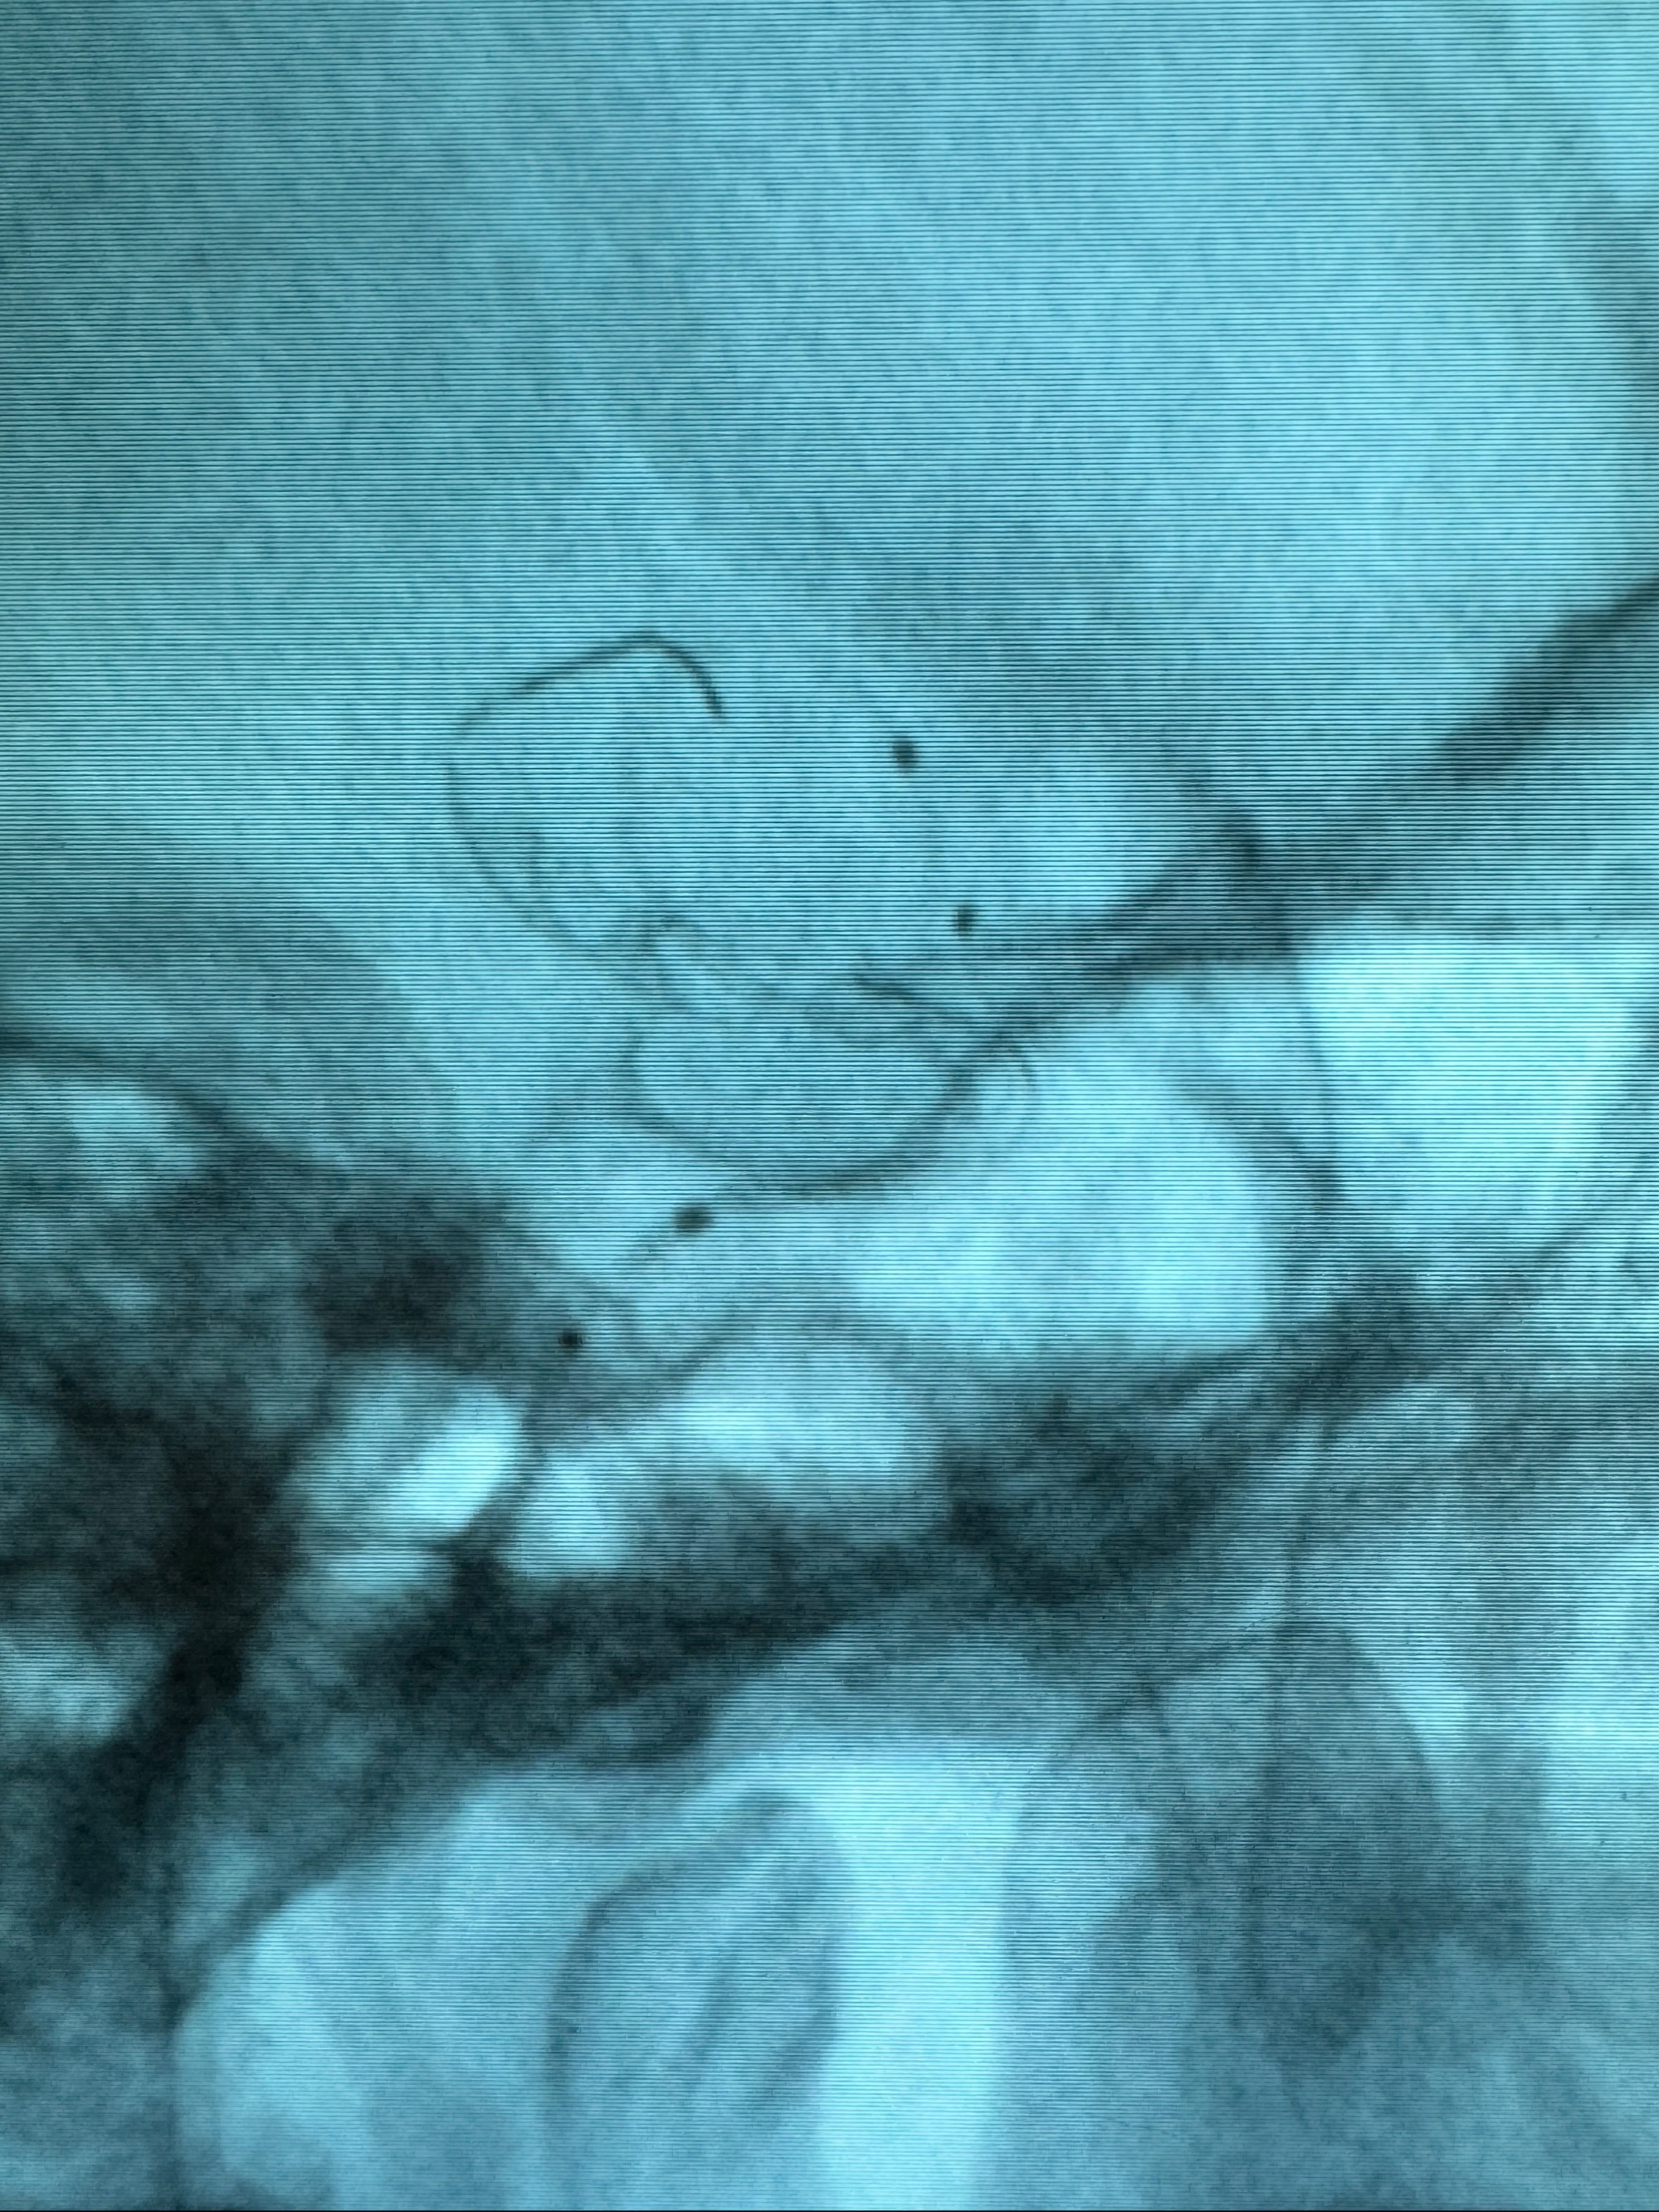

接下的视频为释放支架的过程及试图确认支架与血管的关系

最后再看看颅内血管是否有异常

看动脉瘤内造影剂滞留,未见明确射流,遂撤出预留的栓塞微导管,快速结束手术,经导引导管灌注替罗非班250ug。